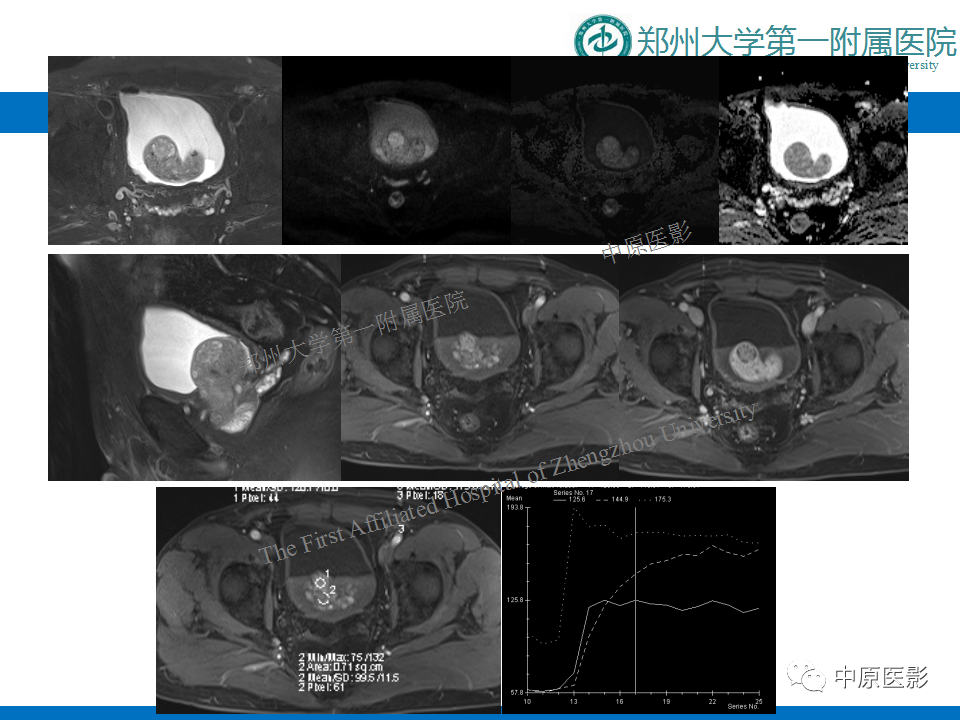

前列腺滑膜肉瘤1例MR影像

【病例】前列腺滑膜肉瘤1例MR影像-1